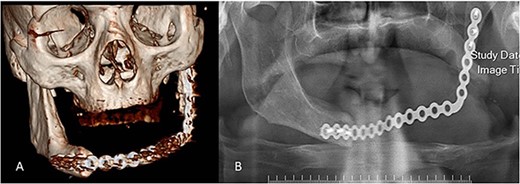

After the complete excision of the lesion (Fig. 3) and reconstruction of the mandible and ramus by the plate, the sample was sent for histopathologic evaluation.

Complete surgical excision of the lesion and reconstruction of the mandible and ramus.

No evidence of recurrence was observed after 2 years (Fig. 8).

Postoperative radiographs. (A) 3D view of the reconstruction plate. (B) Panoramic view of the reconstruction plate after 24 months.